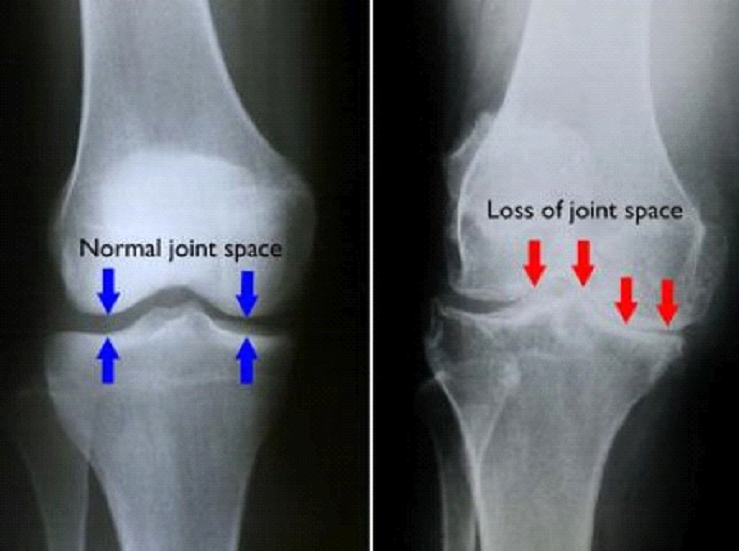

• X-rays to check bone and joint space

(Left) In this X-ray of a normal knee, the space between the bones indicates healthy cartilage (arrows). (Right) This X-ray of an arthritic knee shows severe loss of joint space.